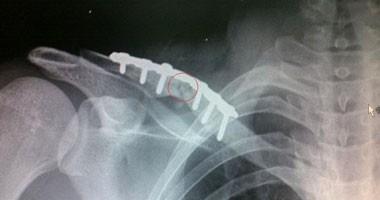

تقنية جديدة فى علاج الكسور العظمية تجنبك استخراج المسامير والشرائح

توصل طبيب ألمانى إلى طريقة جديدة لعلاج الكسور العظمية المعقدة، وذلك من خلال خياطة العظام بالإبرة والخيط، الذى يتحلل فى الجسم بعد أسابيع قليلة من العملية، ما يجنب المريض إجراء عملية ثانية لاستخراج المسامير أو البراغى أو غيرها.

أما فيما يخص ما توصل إليه الطبيب الألمانى فإن عملية الخياطة تتم بخيط بلاستيكى طبى يتحلل فى الجسم بعد أسابيع قليلة من إجراء العملية، الأمر الذى يجعل تقنية خياطة العظام مفيدة للأطفال، إذ تجنب هذه التقنية الجديدة إجراء عملية أخرى لإزالة الشرائح المعدنية، وبهذا يتجنب الأطفال الضغط النفسى، الذى يتم خلال إجراء جراحة أخرى لإزالة الشرائح المعدنية.